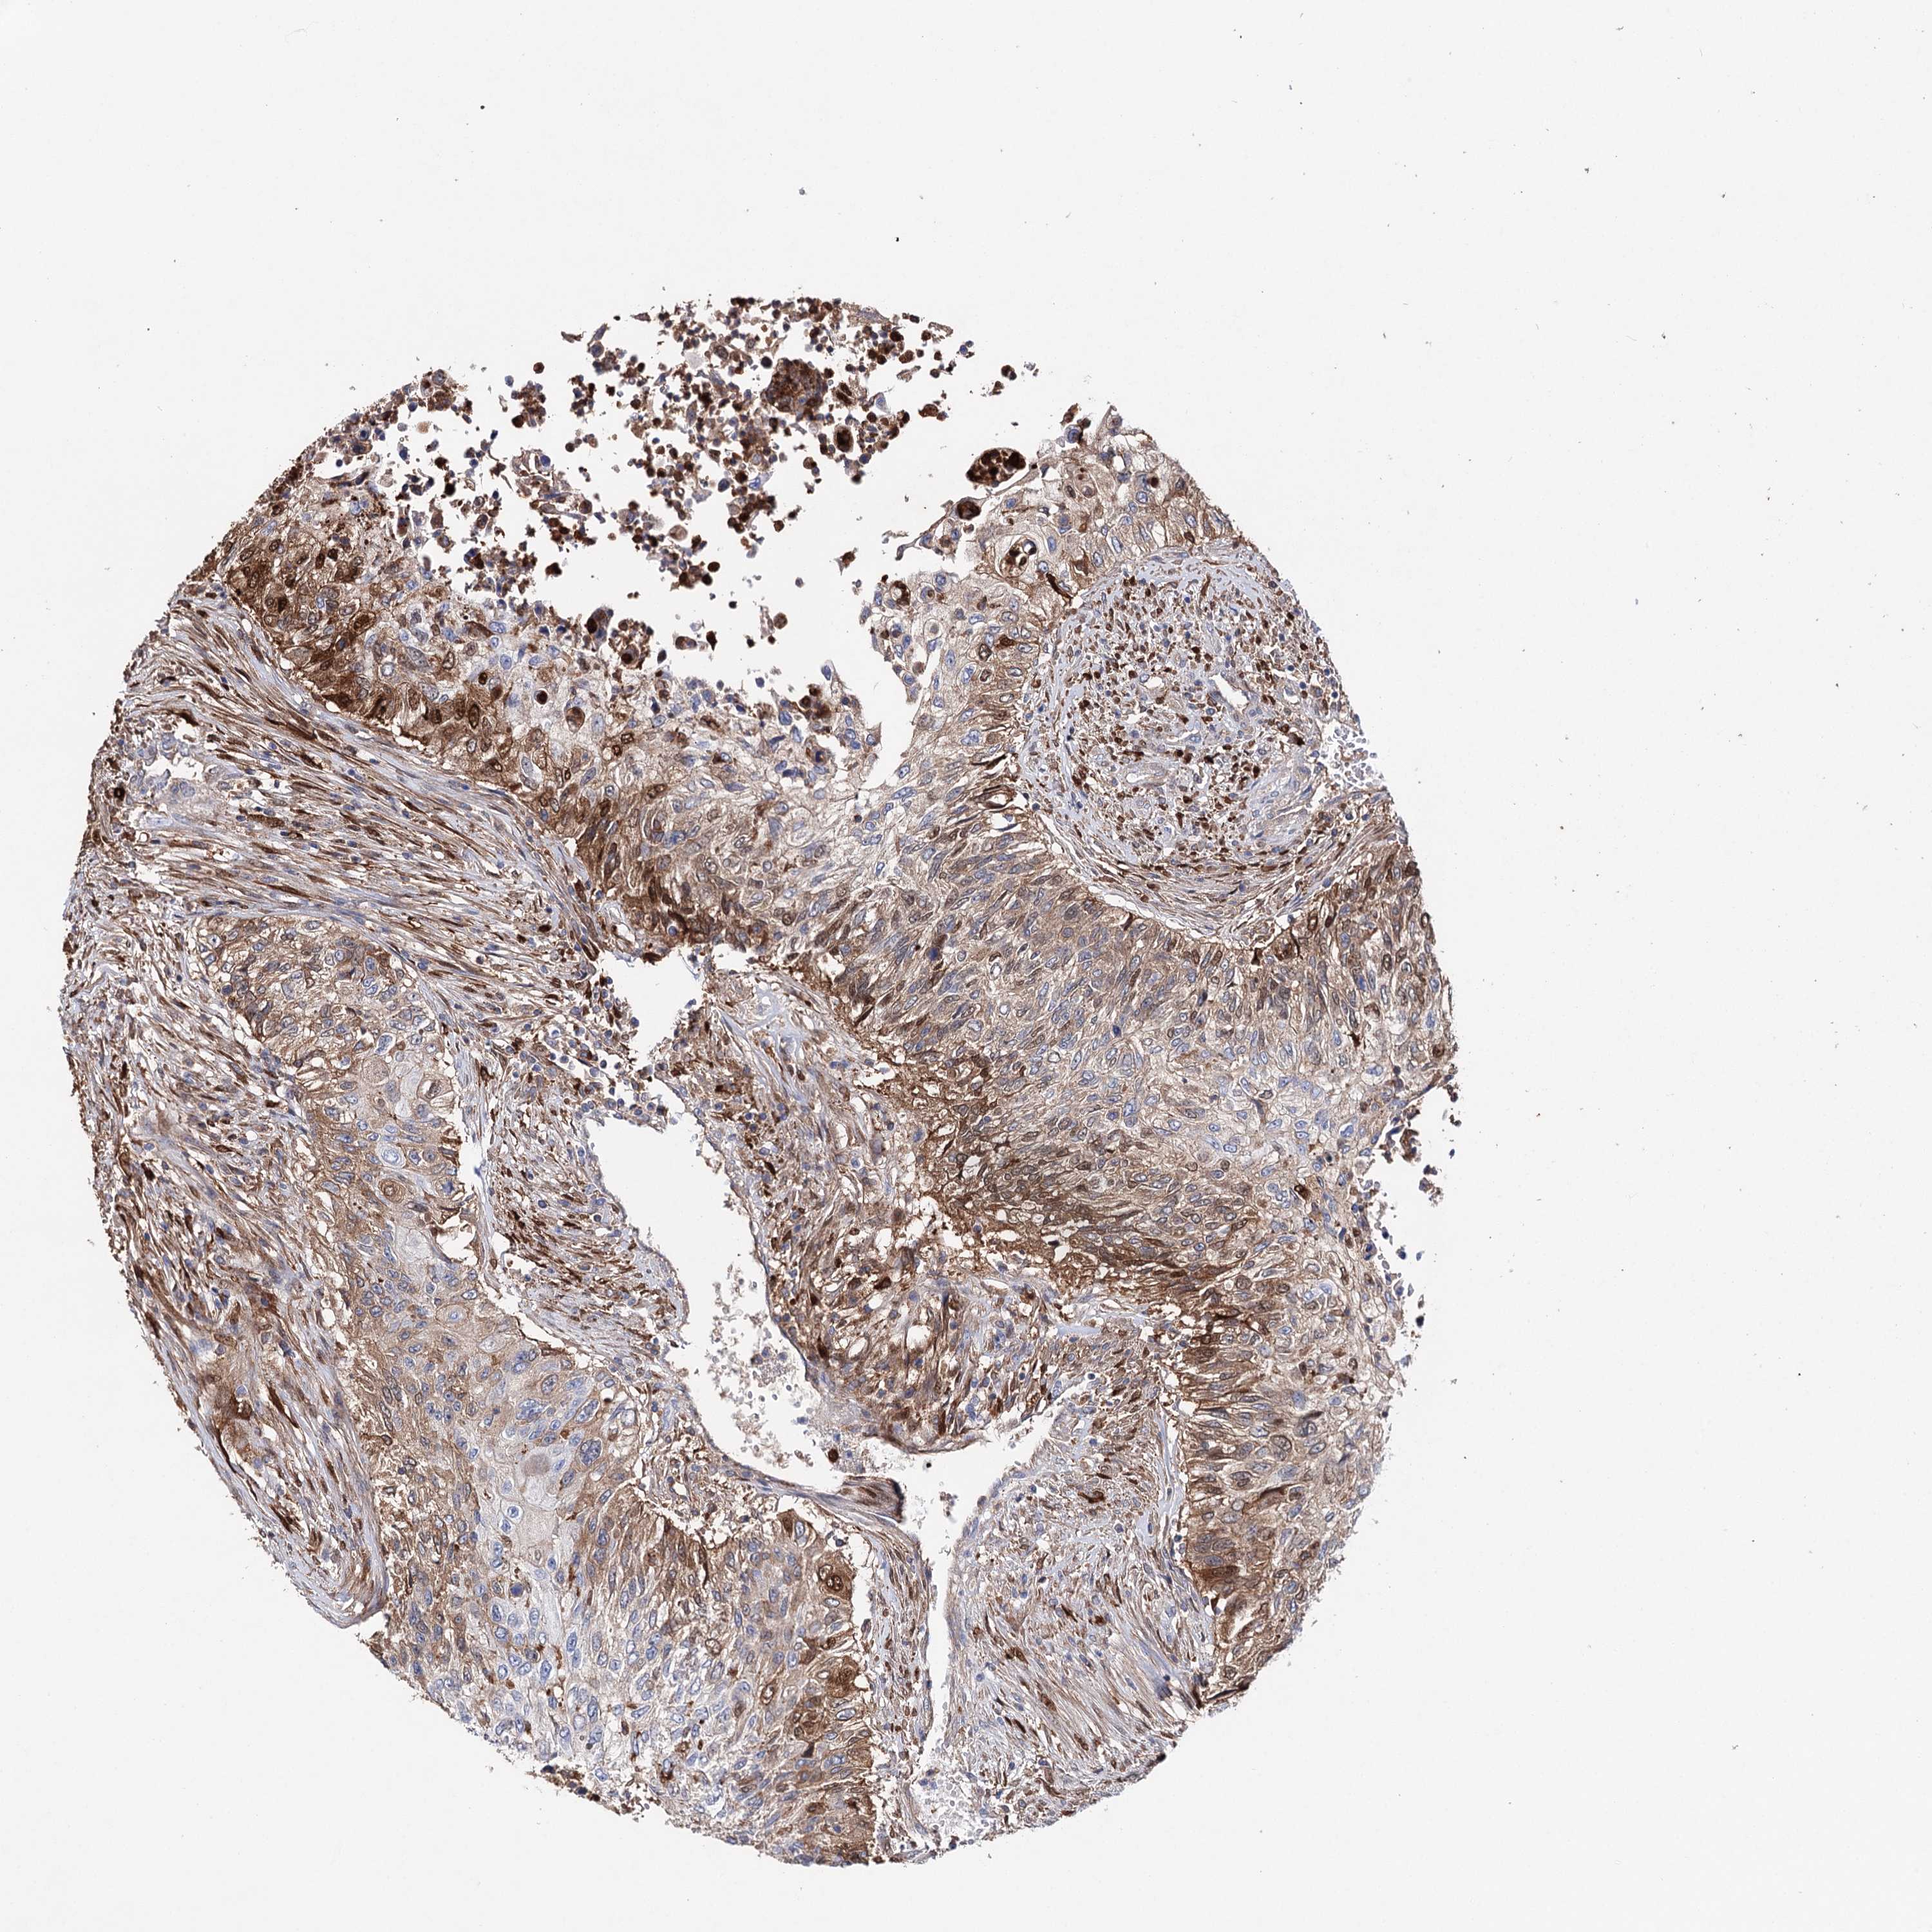

UROTHELIAL CANCER - Protein expressioni

A mouse-over function shows sample information and annotation data. Click on an image to view it in a full screen mode. Samples can be filtered based on level of antibody staining by selecting one or several of the following categories: high, medium, low and not detected. The assay and annotation is described here.

Note that samples used for immunohistochemistry by the Human Protein Atlas do not correspond to samples in the TCGA dataset.

Antibody stainingi

Antibody staining in the annotated cell types in the current human tissue is reported as not detected, low, medium, or high, based on conventional immunohistochemistry profiling in selected tissues. This score is based on the combination of the staining intensity and fraction of stained cells.

Each image is clickable and will lead to virtual microscopy that enables deeper exploration of all samples and also displays staining intensity scores, fraction scores and subcellular localization as well as patient and tissue information for each sample.

Antibody HPA037786

Antibody HPA038034

Antibody HPA038867

Antibody HPA038868

Staining

High

Medium

Low

Not detected

Intensity

Strong

Moderate

Weak

Negative

Quantity

>75%

75%-25%

<25%

None

Location

Nuclear

Cytoplasmic/membranous

Cytoplasmic/membranous,nuclear

Urothelial carcinoma, High grade

Urothelial carcinoma, Low grade

Urothelial carcinoma, NOS